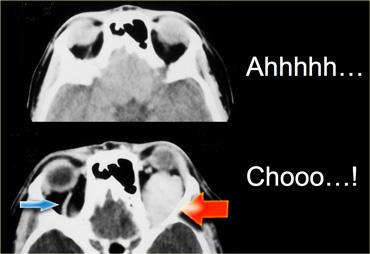

Bên trái là hình ảnh của một bệnh nhân bị giãn tĩnh mạch hốc mắt, người này nhận thấy mắt trái bị lồi ra khi rặn.

Hình trên là lúc nghỉ ngơi và hình dưới là trong nghiệm pháp Valsalva tại thời điểm hắt hơi.

Trong nghiệm pháp Valsalva, tĩnh mạch giãn giãn nở cực độ (mũi tên đỏ).

Lưu ý rằng trong nghiệm pháp Valsalva, tĩnh mạch mắt trên ở bên bình thường cũng giãn ra (mũi tên xanh).Kết luận